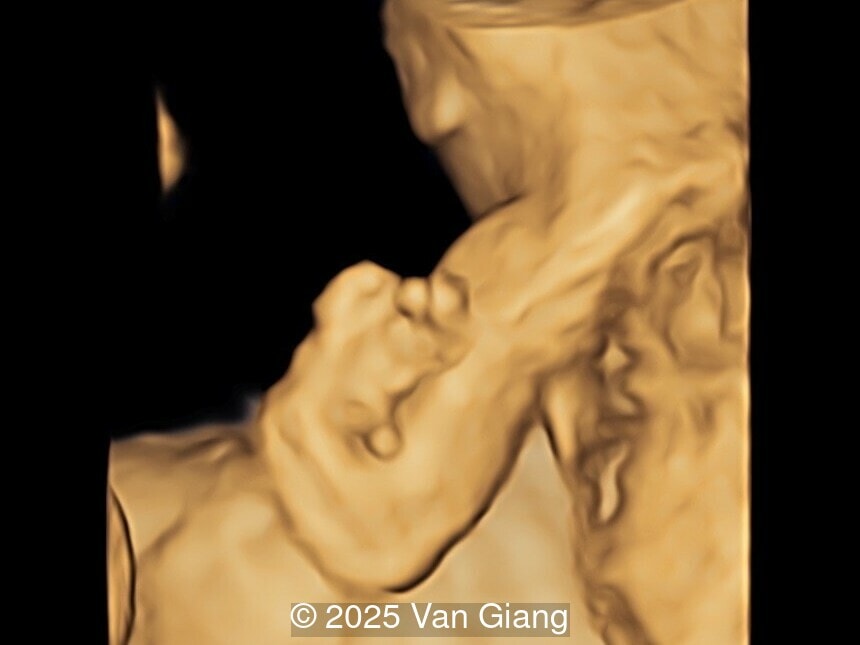

Image 4

Ultrasound revealed severe mandibular and zygomatic hypoplasia, glossoptosis, cleft palate, and micrognathia with an abnormal facial profile. Both upper limbs showed radial ray sequence with abnormal thumbs and shortened forearms. Unilateral clubfoot was also noted. No major cardiac or visceral anomalies were observed. Based on these findings, Nager syndrome was suspected.

Left hand

Image 4 Left hand